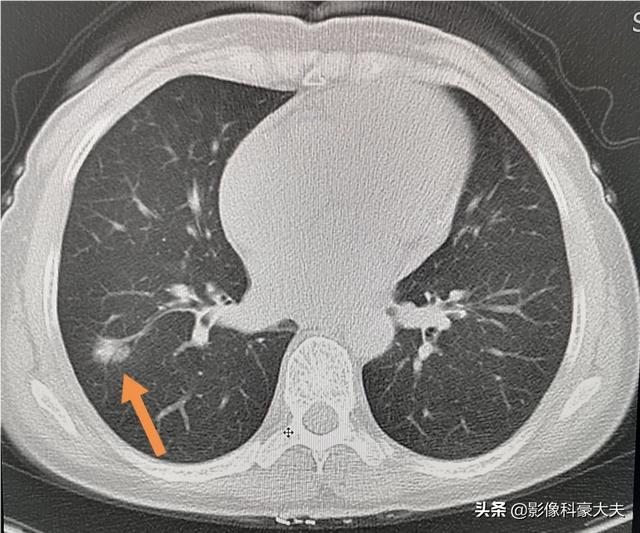

所以肺癌的早期筛查很重要。早期可以治愈!筛查首选胸部螺旋CT。可以及时发现有风险的肺结节。

像这种通过体检及时发现的小肺癌。很常见!每年都治愈很多!